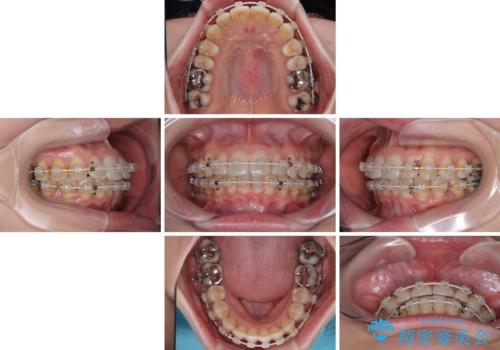

- 矯正装置

- 審美装置

- 治療期間

- 1年3ヶ月

お仕事柄、マウスピース装着は困難とのことで、表側のワイヤー矯正にて治療を行うこととしました。

デコボコ解消の際に、前歯が前突するリスクがあったため、舌突出癖の改善と、アンカースクリューによる加強固定を行うこととしました。

矯正治療後には奥歯の銀歯やむし歯をセラミックやゴールドにて治療を行い、大変整った口腔環境へと改善さ。れました